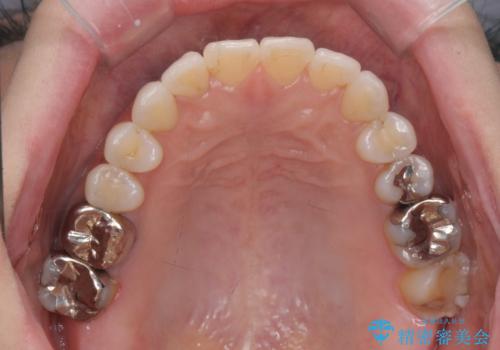

抜歯をせず前歯の角度を改善するマウスピース矯正治療

- 突き出た前歯の角度を改善したい、と矯正治療を希望され来院されました。

抜歯を行いワイヤー矯正で2-3年程度の時間をかけて、しっかり前歯を後方に移動させるか、

抜歯を行わずにIPR(歯の間に空隙を設ける)で可及的に角度の改善を行うか、

2通りの治療方針をご提案しました。

治療期間が約半年で行うことができ、歯を抜かずにマウスピース矯正で可及的に前歯の角度を改善する治療方針を

奥歯の状態等も鑑みて選択されました。

約半年で大きく前歯の角度を改善することができ、抜歯を行わない矯正治療の結果に大変喜んでいただくことができました。